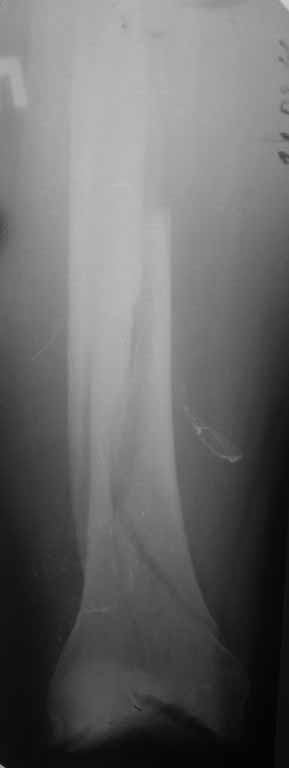

Еще один очень важный нюанс при лечении диафизарных переломов бедра и голени - это лигаментотаксис. Простыми словами, перелом нужно достаточно растянуть. Нам известно три способа как это сделать:

В данному случае, в том числе, перелом не был достаточно растянут. Во многих случаях (преимущественно все-таки при многооскольчатых переломах) именно тракция является основным репонирующим моментом, который и восстанавливает длину и ось. Остается только следить за ротацией. Мышечно-фасциальные футляры во время тракции восстановят правильные соотнешения, если только нет интерпозиции.

Представляю вам один из наших недавних случаев выполнения малоинвазивного остеосинтеза бедренной кости обычной пластиной 95 градусов. Длина восстановлена с помощью дистрактора (по сути это основная и б(о)льшая часть репозиции). Произведено два небольших доступа, проведена спица направитель. Рентген-контроль для подтверждения достаточной длины/оси (ЭОП использовался в другой операционной). Создание туннеля обратной стороной фиксатора. Поворот фиксатора, введение клинка по спице. Фиксация проксимального и дистального концов пластины.